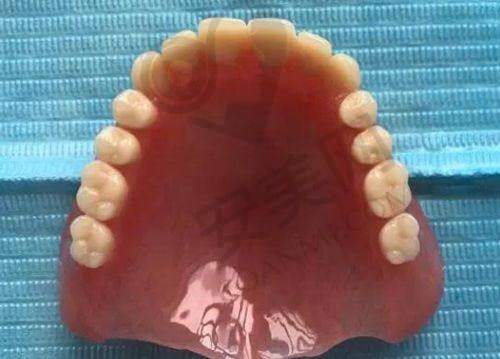

从众多患者的反馈来看,重庆美奥口腔医院的口碑较好。患者们普遍认为医院的医生技术好、服务态度佳,收费合理,环境和设备也不错。有患者分享了75岁大爷在重庆美奥口腔做bps吸附性义齿的经历,还有患者讲述了自己在重庆美奥口腔拔牙、矫正牙齿的过程,都对医院的治疗成效和服务质量表示满意。